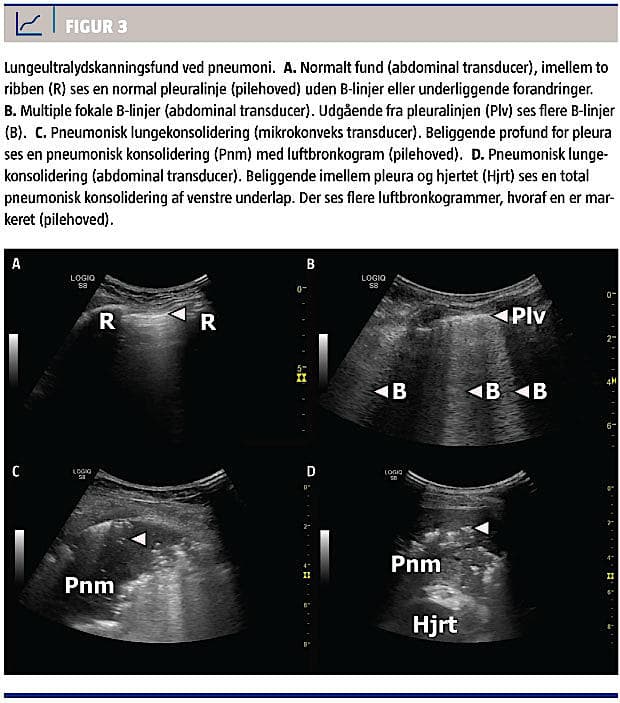

NORMALE FUND

En pneumoni, som udelukkende afficerer dybtliggende dele af lungen og dermed ikke medfører en ændring i densiteten af det lungevæv, som er beliggende lige under pleura viscerale, kan ikke visualiseres med LUS. Pleuralinjen fremtræder normal uden B-linjer, og der er ingen synlige områder med lungekonsolidering (Figur 3A).

FOKALE B-LINJER

Ved en let øget densitet i lungevævet opstår der artefakter, der benævnes B-linjer. En B-linje er en hyperekkoisk, hvid, vertikal linje, der udgår fra pleura og strækker sig usvækket igennem billedet (Figur 3B).

LUNGEKONSOLIDERING

En pneumoni, der har medført konsolidering af lungeparenkymet lige under pleura viscerale, visualiseres direkte med LUS. Den pneumoniske konsolidering fremtræder som et hyperekkoisk, gråt område, der sonomorfologisk kan minde om strukturen i leveren eller milten. Pneumoni er kendetegnet ved et irregulært og uskarpt afgrænset område, hvor der i randzonen ofte forekommer B-linjer. Desuden er det karakteristisk for pneumoni, at der findes luftbronkogrammer (Figur 3C og Figur 3D). Fænomenet kendes også fra røntgen- og CT-billeder og skyldes, at der er luftholdige bronkier i det inflammerede, konsoliderede

lungevæv. Med LUS ses luftbronkogrammer som

hyperekkoiske, hvide linseformede elementer eller som forgreninger inde i konsolideringen. De kan variere i diameter og flytte sig synkront med respirationen [8].